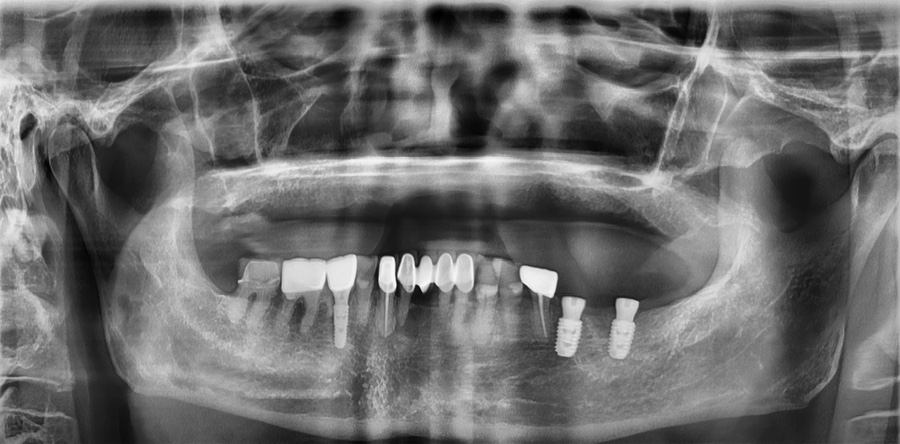

치료 전 사진 / 2024. 12. 18

치과 치료를 시작하기 전에는 현재 구강 상태를 정확히 파악하는 것이 중요합니다.

파노라마 엑스레이 등을 통해 치아, 잇몸뼈, 염증 여부를 확인하면 단순 치료인지, 임플란트나 발치가 필요한지 판단할 수 있습니다.

특히 치주염이나 치아 손상이 심한 경우에는 보존이 어려워질 수 있고, 치아 상실을 방치하면 뼈가 흡수되어 치료가 더 복잡해질 수 있습니다.

따라서 정확한 진단을 바탕으로 적절한 치료 계획을 세우는 것이 무엇보다 중요합니다.